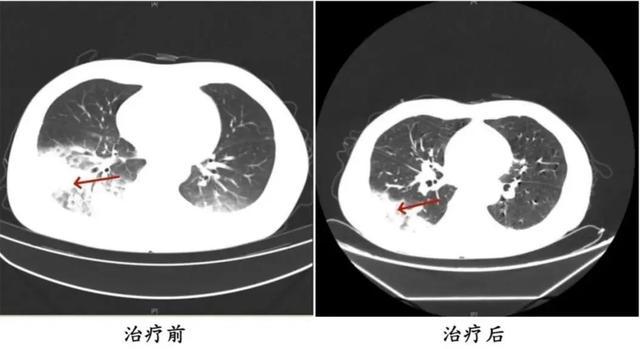

家人见状,立即将他送医。胸部CT显示李先生的左肺已出现大面积白色影像,几乎占据一半肺部。经过检测,最终确认是 嗜肺军团菌肺炎。

李先生肺部治疗前与治疗后的对比